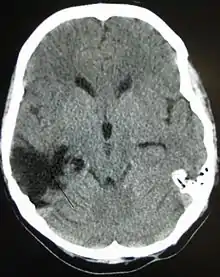

تظهر الإصابة المنتشرة في التصوير العصبي مع القليل من الضرر الواضح، ولكن يمكن رؤية الآفات مع التقنيات المجهرية بعد الوفاة.[18][19] وفي أوائل الألفية الثانية، اكتشف الباحثون أن صورة الانتشار في الرنين المغناطيسي، وهي سيلة معاَلجة للتصوير بالرنين المغناطيسي تظهر مسارات المادة البيضاء، كانت أداة فعالة لعرض مدى إصابة المحور العصبي المنتشرة.[20][21] وتشمل أنواع الإصابات التي تعتبر منتشرة وذمة (تورم) وإصابة المحور العصبي المنتشرة، وهو عبارة عن حدوث الأضرار واسعة النطاق للمحاور العصبية بما في ذلك مسارات المادة البيضاء والنتوءات إلى القشرة.[22][23]

الأورام الدموية، هي أيضًا إصابات بؤرية، وهي عبارة عن تجمعات من الدم في أو حول الدماغ يمكن أن تنتج عن النزف.[3] النزيف المخي هو آفة داخل المحور نفسه حيث تنزف أنسجة المخ نفسها. بينما تشمل الآفات خارج المحور الورم الدموي فوق الجافية، الورم الدموي تحت الجافية، ونزف تحت العنكبوتية، والنزيف داخل البطين.[31] ينطوي الورم الدموي فوق الجافية على نزيف في المنطقة بين الجمجمة والأم الجافية، الغشاء الخارجي من الأغشية الثلاثة المحيطة الدماغ.[3] وفي الورم الدموي تحت الجافية، يحدث النزيف بين الأم الجافية والأم العنكبوتية.[15] بينما ينطوي نزف تحت العنكبوتية على النزيف في الفضاء بين الغشاء الأم العنكبوتية والأم الحنون.[15] ويحدث النزيف داخل البطين عندما يكون هناك نزيف في الجهاز البطيني.[31]